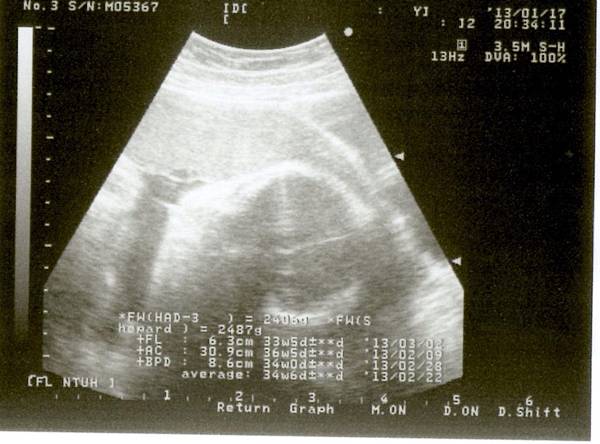

這次產檢隔一周是因為下周正逢農曆過年, 醫院門診休息~所以就提前一周來做檢查~

從上周到這週的不適狀況已逐漸消除(如腳部極癢, 便秘嚴重,分泌物增多), 但有了新的現象發生-就是胎動非常的明顯!!

以前都覺得Q比較懶都不喜歡動,但現在發現卻不是這一回事~她三不五時就在動, 尤其是她那有力的雙腳~